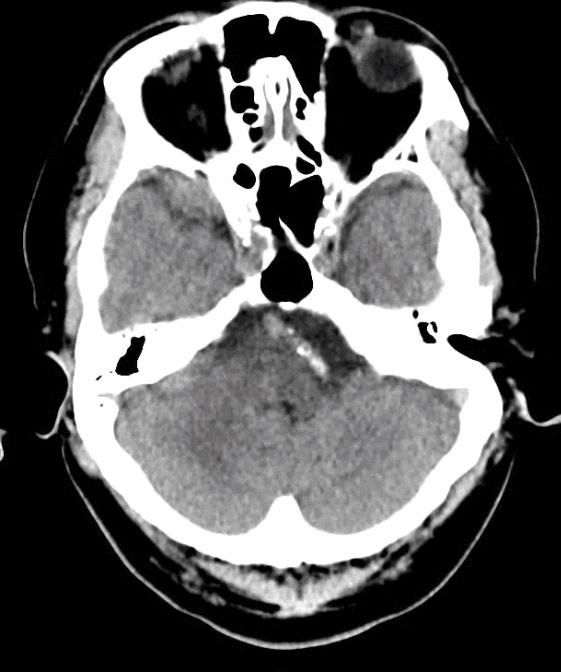

术前影像学检查

我院完善颅脑CT+CTA+MRI。

左侧颈总入路迂曲。

长鞘+125cm单弯+加硬导丝建立通路;Tethys®中间导引导管+0.014inch微导丝+10微导管。

导丝通过病变段。

微导管跟进。

确认系统位置,交换3m 0.014inch微导丝。

加奇1.75mm×9mm SacSpeed®球囊扩张导管顺利到位。

缓慢扩张。

扩张后前向血流仍较差。

重新调整入路后再次造影。

3m 微导丝配合微导管再次接近病变。

更换微导丝兼顾支撑及操纵性,协助微导管过病变段后交换3m 0.014inch微导丝。

使用SacSpeed®球囊扩张导管再次扩张。

扩张后前向血流好转。

引入3mm×21mm支架覆盖病变。

支架释放后造影。

术后3D。